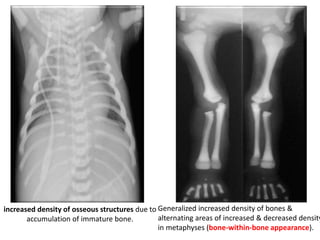

sandwich vertebrae /

rugger jersey appearance

increased density of osseous structures due to

accumulation of immature bone.

Generalized increased density of bones &

alternating areas of increased & decreased density

in metaphyses (bone-within-bone appearance).